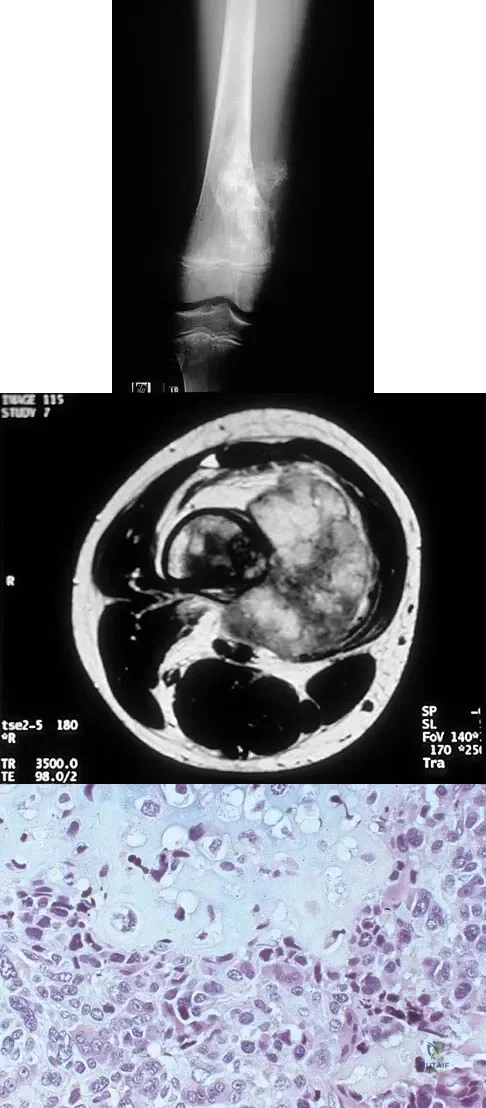

A 21-year-old man has had progressive right knee pain for the past 2 months that is exacerbated with weight-bearing activities. A plain radiograph and an MRI scan are shown in Figures 43a and 43b. A biopsy specimen is shown in Figure 43c. According to the Enneking staging system of tumor classification, the lesion should be classified as what stage?